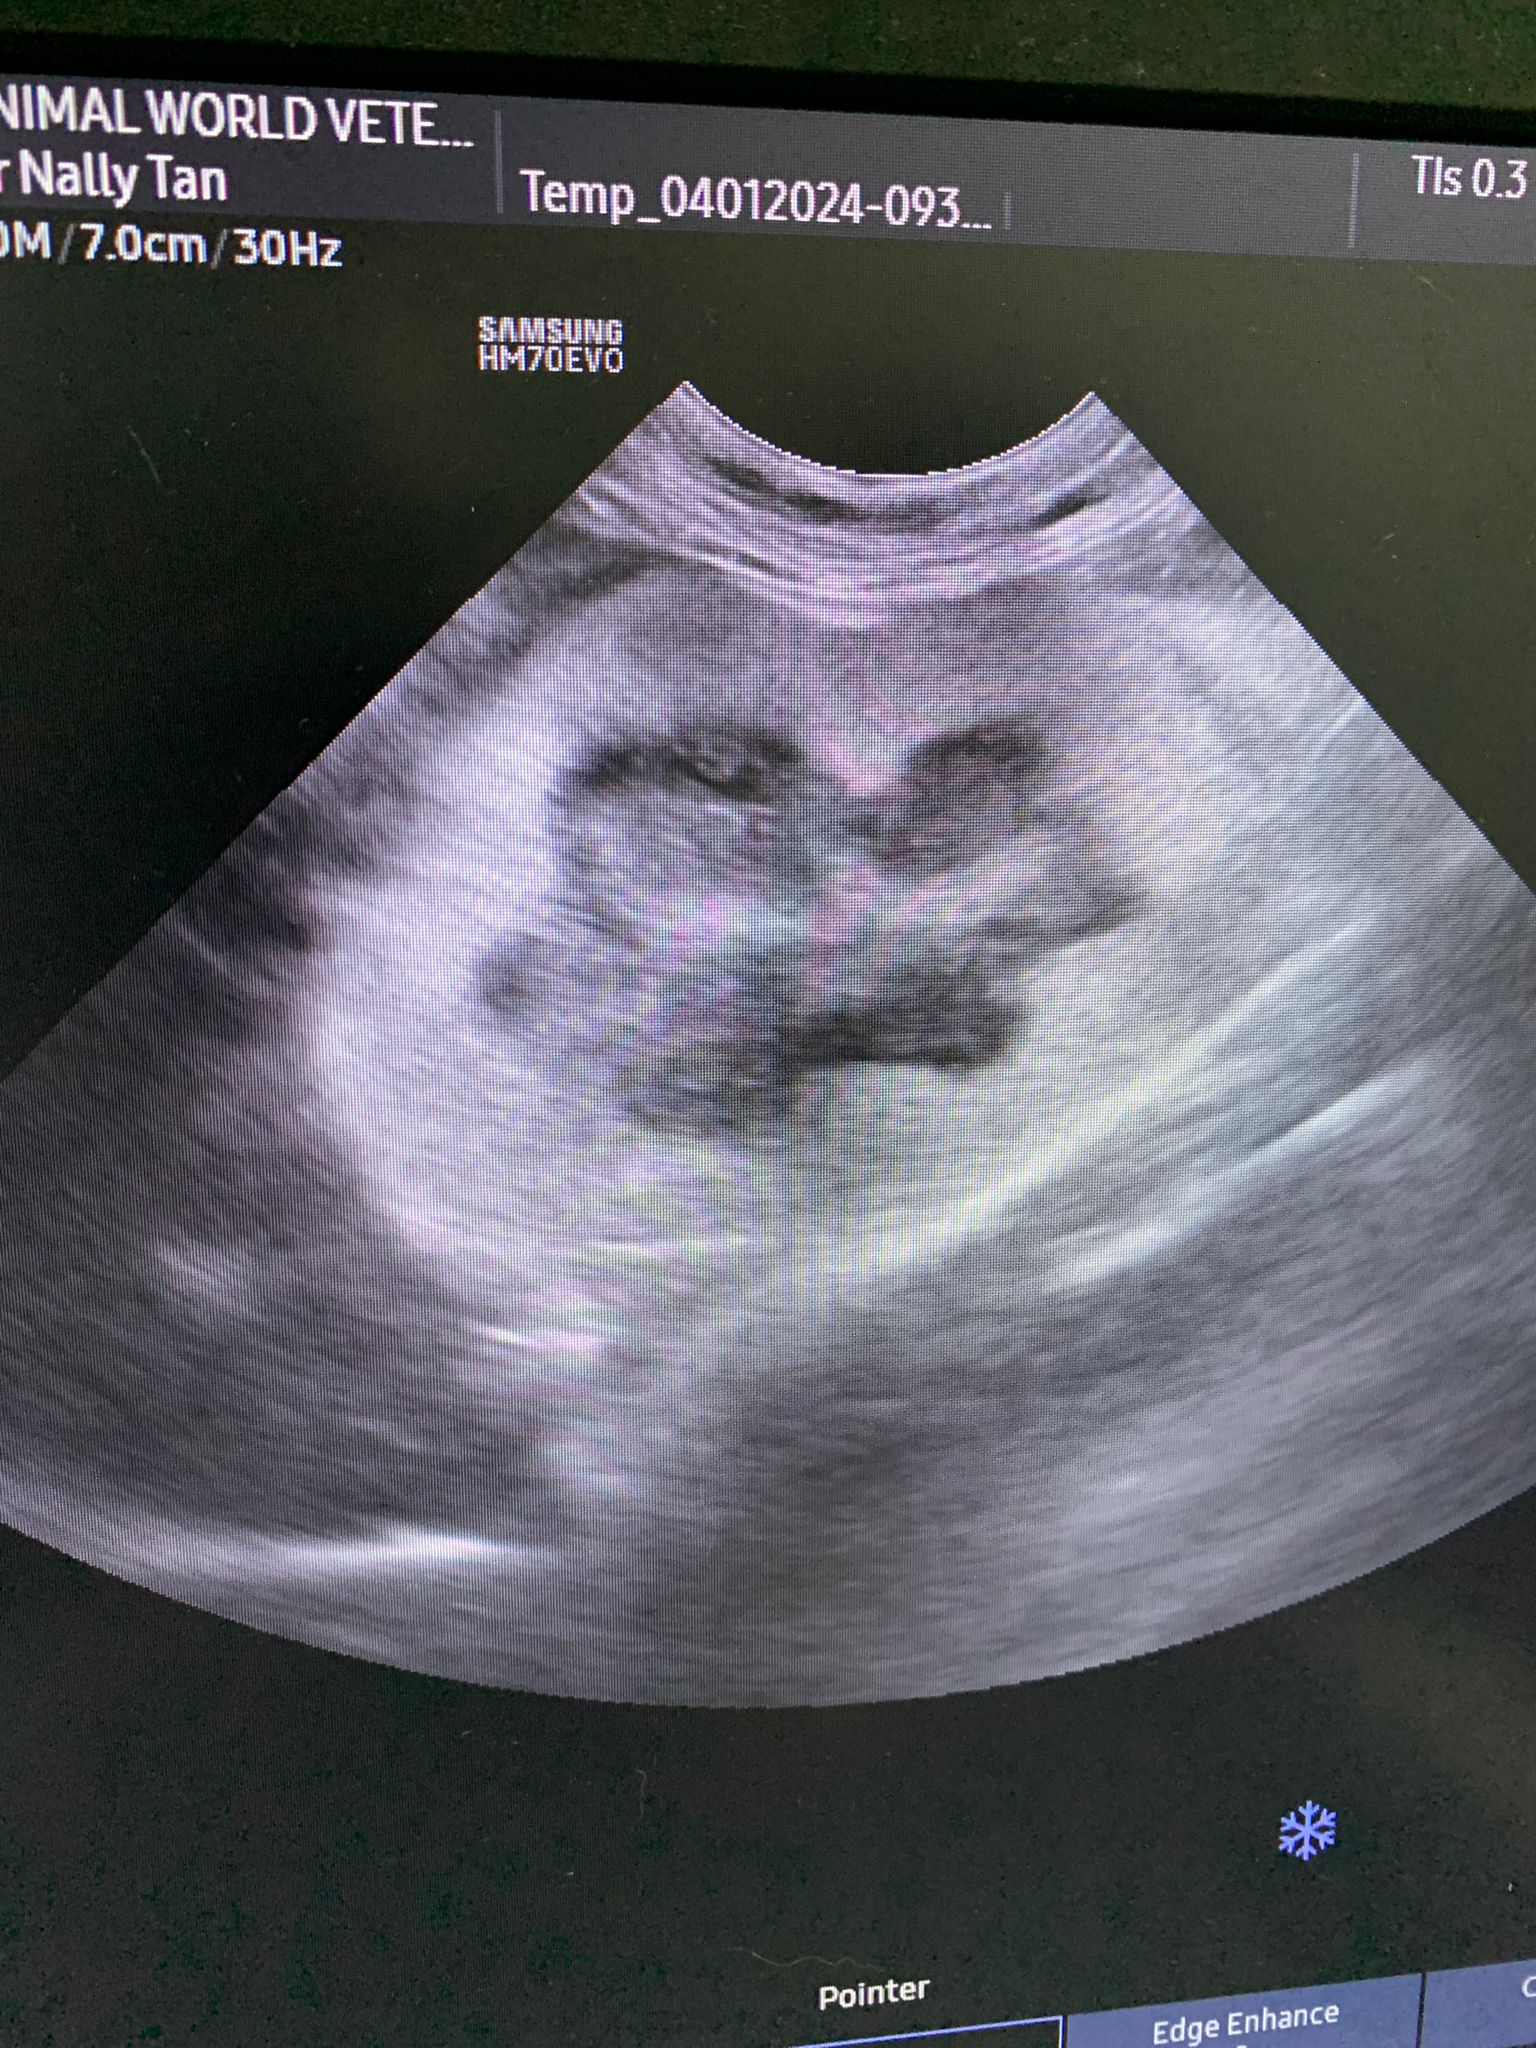

Dr ym scan sweeties, dr flo not involve, both got free fluid ard the kidneys, left kidney is extremely abnormal, right kidney abnormal.

U/s still show the scary fluid ard the kidneys and there is issue w gall bladder also. As the GGT 7 but without confirming is it an obstruction cannot anyhow use. Give le obstruct will rupture.

there is fluid ard her kidney, and the enlarged kidney is pressing onto her intestines, so that may cause some discomfort and issue w her pooing. But dr nally think she can poo on her own la.just that maybe pain she didn’t even want to try to poo.